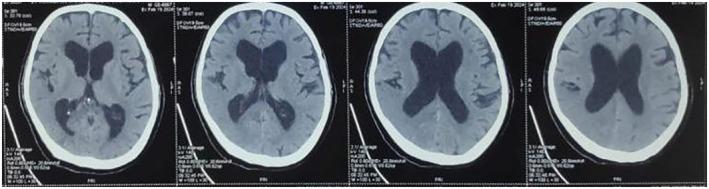

Belly dancer's dyskinesia (BDD) is characterized by bilateral, sluggish, involuntary, repetitive, and rhythmic motions of the anterior abdominal wall. We present a rare case of a 78-year-old man diagnosed with normal pressure hydrocephalus associated with BDD and seizure who presented with left-sided weakness of the body and abnormal body movements.